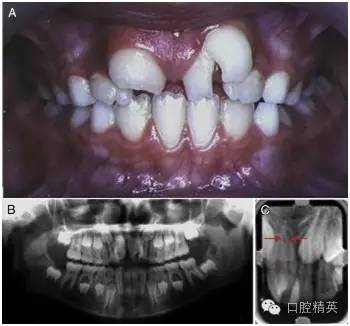

2002 年,一位左上中切牙巨大的 9 歲女孩因抱怨美觀問題而被轉(zhuǎn)診過來(圖 1)。經(jīng)初步檢查,患者口腔中剩余的其他乳牙與恒牙大小和形狀都表現(xiàn)正常,牙齒數(shù)量上無減少。患者家族史與既往病史不詳。

圖 1 左上巨牙癥術(shù)前資料。(A)口內(nèi)正面像。(B)x 線全景片。(C)根尖片,箭頭所指處表明兩顆牙齒的根管影像是分開的。

進(jìn)一步檢查發(fā)現(xiàn),一顆形狀不規(guī)則的多生牙與左上中切牙在冠部頸 1/3 處融合在了一起。然而,通過全景片與根尖片可以判斷出兩顆牙的根管影像是各自分開的 (圖 1-B,1-C[ 箭頭處])。這可以被認(rèn)為是一條垂直向的發(fā)育溝把牙冠從近中 1/3 處分成兩個(gè)錐形牙冠造成的并生。患牙牙冠近遠(yuǎn)中總寬度為 15mm,而正常的右上中切牙牙冠近遠(yuǎn)中寬度只有 10mm。

由此造成的切牙區(qū)域的擁擠導(dǎo)致了融合牙遠(yuǎn)中部分的唇傾(作為整體來描述則是遠(yuǎn)中頰側(cè)扭轉(zhuǎn))。對(duì)融合牙用冷測(cè)法進(jìn)行牙髓溫度測(cè)試,測(cè)試結(jié)果為正常。

根據(jù) x 線片,可以清楚地觀察到兩個(gè)明顯的牙根因融合的牙骨質(zhì)連在了一起。結(jié)合口內(nèi)臨床檢查可以確定,這是由一顆不規(guī)則的多生牙與左上中切牙融合在一起的融合牙。檢查過程中,未發(fā)現(xiàn)牙髓與根尖周組織存在其他的異常。